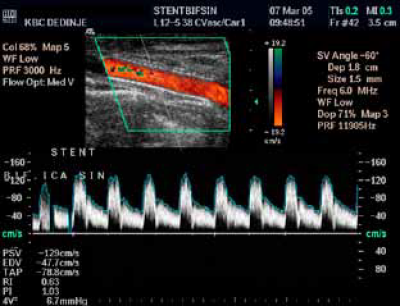

Karotidna restenoza na samoj bifurkaciji, glatke površine (A), Restenoza je rešena plasiranjem stenta.

Implantacija stenta u bifurkaciju zbog karotidne restenoze – Power Doppler uredan kontrolni follow up nalaz. Nema restenoze

Spektralna analiza, uredan nalaz po implantaciji stenta zbog resstenoze

Implantacija stenta u bifurkaciju

zbog karotidne restenoze.

Uredan kontrolni follow up nalaz.

Nema restenoze